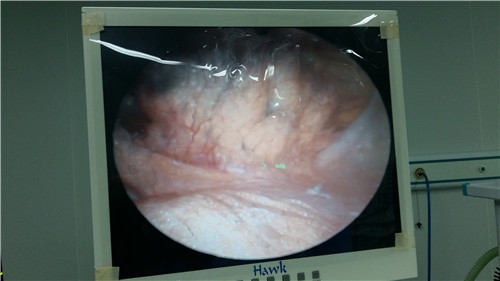

毕业于吉林大学,从事三甲医院骨科临床工作20余年,在脊柱、关节、四肢及手足等专业领域具有丰富的临床经验,擅长人工关节置换、脊柱非融合固定、断肢再植及四肢瘫手功能重建、拇外翻微创矫形等特色技术。

脊柱、关节、四肢及手足疾病